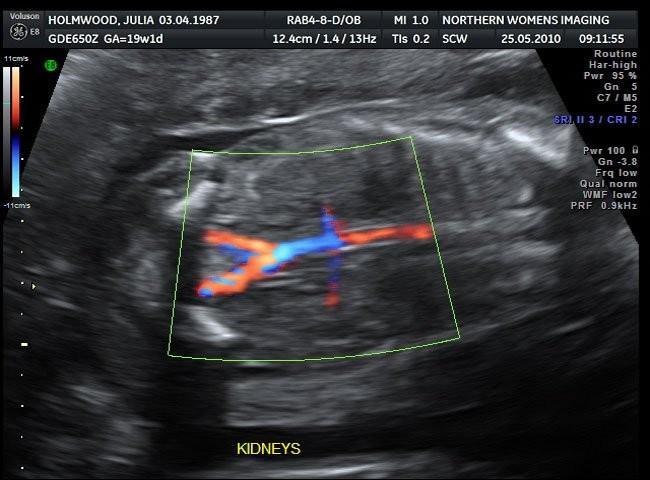

Dentro de las pruebas prenatales de seguimiento del embarazo encontramos una ecografía especial que no se realiza por rutina. Es la ecografía doppler, la cual mediante color y sonido, permite observar el flujo de los vasos sanguíneos.

Suele realizarse hacia el final del embarazo, en el último trimestre, para medir y evaluar el flujo de sangre que recibe el bebé a través del cordón umbilical.

La ecografía doppler permite ver en detalle el funcionamiento del corazón del bebé, así como analizar las válvulas cardíacas y las paredes del corazón. Por tanto, se utiliza como método para detectar de forma precoz cualquier malformación o anomalía cardiaca que pudiera tener el bebé.

En casos de sospecha de retraso de crecimiento fetal la ecografía doppler también es muy útil. Sirve para controlar las arterias umbilicales y el flujo de sangre que le llega al bebé, y por ende los nutrientes y el oxígeno que recibe a través de la placenta.

También es especialmente útil en caso de hipertensión de la madre, diabetes, problemas en la placenta o el cordón umbilical o sufrimiento fetal.